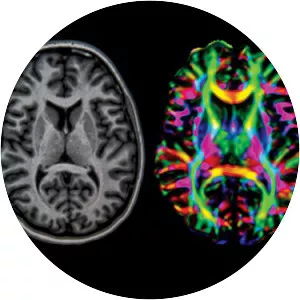

Neuroradiology is a subspecialty of radiology focusing on the diagnosis and characterization of abnormalities of the central and peripheral nervous system, spine, and head and neck using neuroimaging techniques.